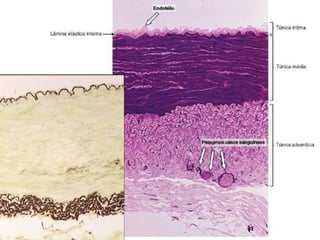

Parede da Artéria Elástica

• Túnica íntima

– Endotélio: epitélio pavimentoso simples

– Camada subendotelial, conjuntivo com fibras colágenas e elásticas,

células musculares lisas e macrófagos

– Membrana elástica interna

• Túnica média

– Possui material elástico circular, entre as quais estão as células

musculares lisas em circular

• Túnica adventícia

– Conjuntivo com fibras elásticas, colágenas, fibroblastos e macrófagos

– Vasa vasorum – vasos que nutrem a parede do vaso sangüíneo

– Nervi vascularis – nervos